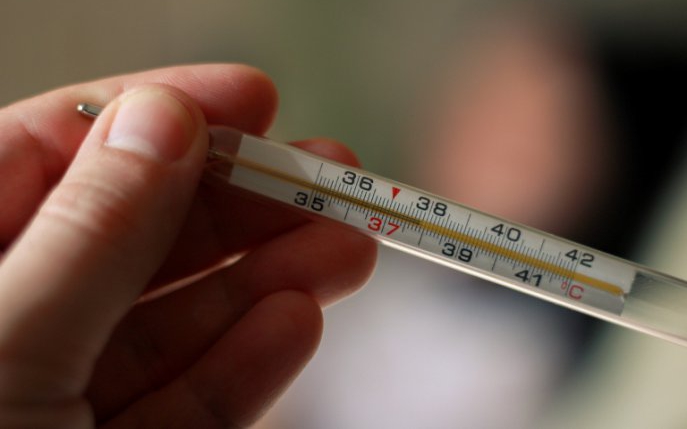

Un bărbat de 32 de ani din China a ajuns la spital acuzând dureri abdominale. Investigațiile au scos la iveală un termometru cu mercur înghițit în copilărie, care a rămas în corpul său timp de două decenii.

Pacientul s-a prezentat la spital, iar o scanare medicală a arătat prezența unui corp străin în duoden, medicii suspectând că este vorba despre un termometru cu mercur, potrivit South China Morning Post.